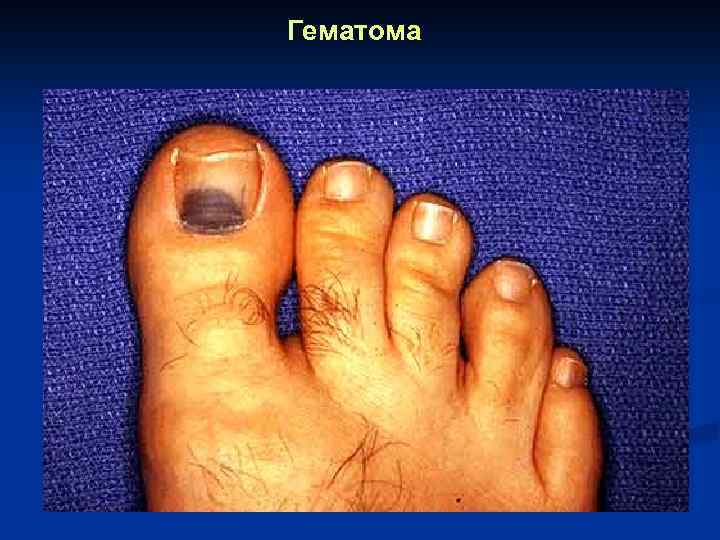

Гематома